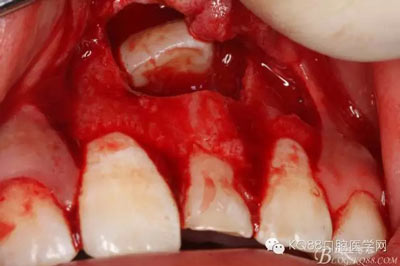

圖8.翻開(kāi)牙齦粘膜瓣,可見(jiàn)左乳Ⅰ根方骨面隆起

圖9.超聲骨刀去除隆起的骨壁

圖10. 形成梯形骨縫